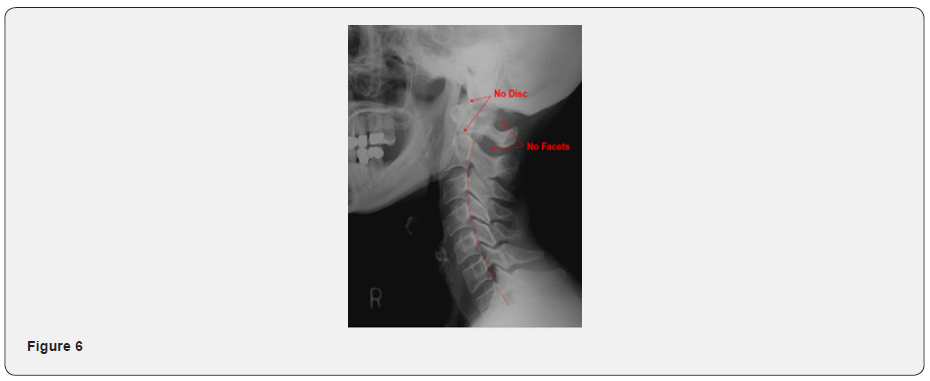

The upper cervical spine is unlike any other vertebral segment of the body. Although vertebrae of the spine are stabilized by intervertebral discs and posterior interlocking facet joints, the transitionary occiput-C1-C2 region does not have these anatomical features. As a result, over 60% of cervical rotation occurs between C1 and C2, and the first 30 degrees of cervical flexion and extension occurs between occiput and C1. This area of the spine has the greatest range of motion, with minimal capacity for osseous fixation as the occiput-C1-C2 joints are a diarthrodial, synovial, freely moveable joint complex (Figure 6). Without the structural stabilizing components, the upper cervical spine is more vulnerable to injuries and malposition. It has been stated that there is no such thing as a head injury that does not also include a neck injury. When considering that the average weight of the adult head is 10-14 lbs., there is substantially increased potential for the craniocervical junction to become subluxated during head or neck trauma, compared to any other, more stabilized joint of the spine. It is quite plausible that most head injuries would also include craniocervical joint injury. Varying directions and degrees of malposition are possible, causing associated dysfunctions and symptomatology.